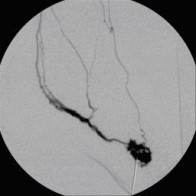

Postoperative abdominelle Blutungen bei chronischer Pankreatitis vor Embolisation der Art. gastroduodenalis mittels Metallspiralen (Coils)

(Bild 2 von 5)